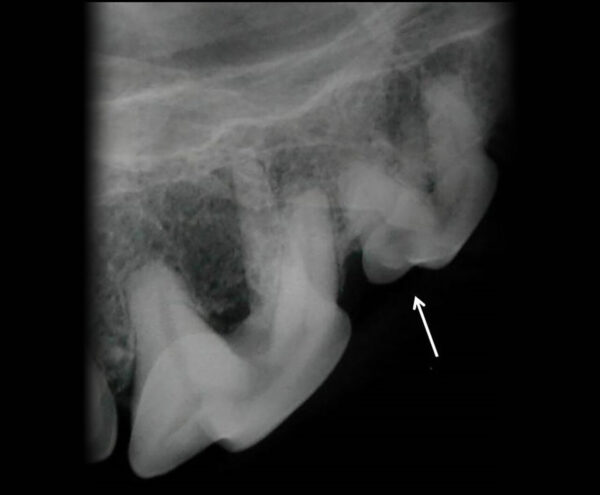

- Grado 2 (PD2): pérdida del soporte óseo menor al 25 % (imagen 7).

- Grado 3 (PD3): pérdida del soporte óseo de un 25-50 % (imagen 8).